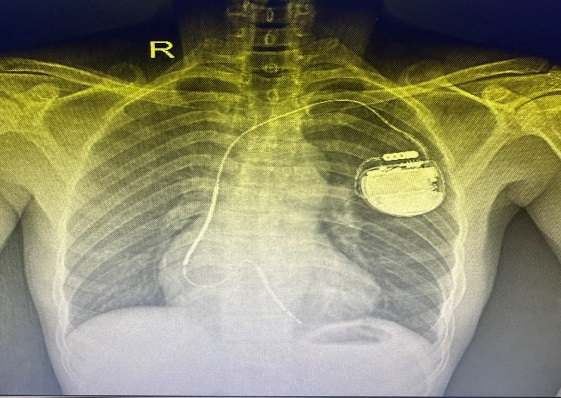

Máy tạo nhịp vĩnh viễn là một thiết bị nhỏ gắn vào cơ thể bệnh nhân để giúp điều chỉnh nhịp tim khi tim không đập đúng cách. Nó giúp bệnh nhân duy trì nhịp tim ổn định, phòng ngừa các triệu chứng như mệt mỏi, chóng mặt, hoặc ngất xỉu, đột tử do tim (ICD), bên cạnh đó còn giúp cải thiện sức co bóp cơ tim ở những bệnh nhân suy tim nặng điều trị nội không đáp ứng (CRT).

Thiết bị này được cấy vào cơ thể bệnh nhân dưới da, thường ở khu vực dưới xương đòn, và kết nối với tim qua một hoặc nhiều dây dẫn.

Hiện nay bệnh viên Đa Khoa Trung Tâm An giang đã thực hiện nhiều kỹ thuật chuyên ngành tim mạch can thiệp trong đó đặt máy tạo nhịp vĩnh viễn được thực hiện từ 2012. Đến nay, thủ thuật đặt máy tạo nhịp tim (bao gồm: máy tạo nhịp một buồng, hai buồng, tái đồng bộ, máy phá rung tự động, máy tạo nhịp không dây) đã được các bác sĩ Khoa Tim mạch lão học duy trì, cứu sống nhiều BN nguy kịch, nâng cao chất lượng cuộc sống.